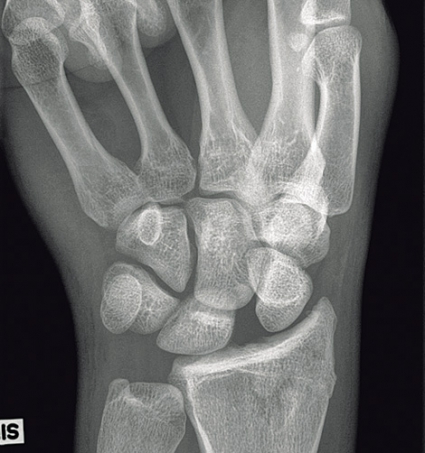

Vi redogör här förenklat för perilunära luxationer och transskafoidala perilunära luxationer. Skadorna består av »lesser arc injuries«, dvs isolerade perilunära ligamentskador, och »greater arc injuries«, dvs där det föreligger samtidiga frakturer av karpalben och/eller styloider. Dessa skador är alltid högenergiskador [9], som t ex trafikolyckor eller fall från hög höjd. De drabbar främst yngre män och utgör ca 7 procent av alla akuta karpala skador.

Ungefär 10 procent av skadorna är öppna. Svårighetsgraden av framför allt de slutna skadorna undervärderas ofta. Så mycket som en femtedel av skadorna missas ofta primärt. Symtom och fynd vid akuta skador är felställning i handleden, som dock lätt kan döljas av svullnaden. Dessutom är rörelseförmågan i handleden nedsatt liksom ibland även fingerrörligheten. Smärtan behöver inte vara uttalad, vilket bidrar till att denna komplicerade skada ibland kan missas akut.

Observera att samtidiga ipsilaterala skador, t ex armbågsluxation, är vanliga. Akut karpaltunnelsyndrom förekommer i ungefär en tredjedel av fallen. Diagnosen ställs på röntgenbilden: Leta efter oordning bland karpalbenen och brutna Gilulas linjer! Observera att luxationen främst framträder på sidobilden, medan frontalbilden kan förefalla närmast normal. Man ska vara frikostig med datortomografi (DT), som kan påvisa mer ovanliga skademönster och synliggöra associerade karpala frakturer. Scaphoideum- och capitatum-frakturer är i detta sammanhang vanligast förekommande. DT kan också underlätta valet av snittföring. Observera att dessa skador alltid kräver öppen kirurgi, även om primär reposition lyckas och kontrollröntgen inte visar några frakturer. Enbart perkutan stiftfixation är aldrig till fyllest.